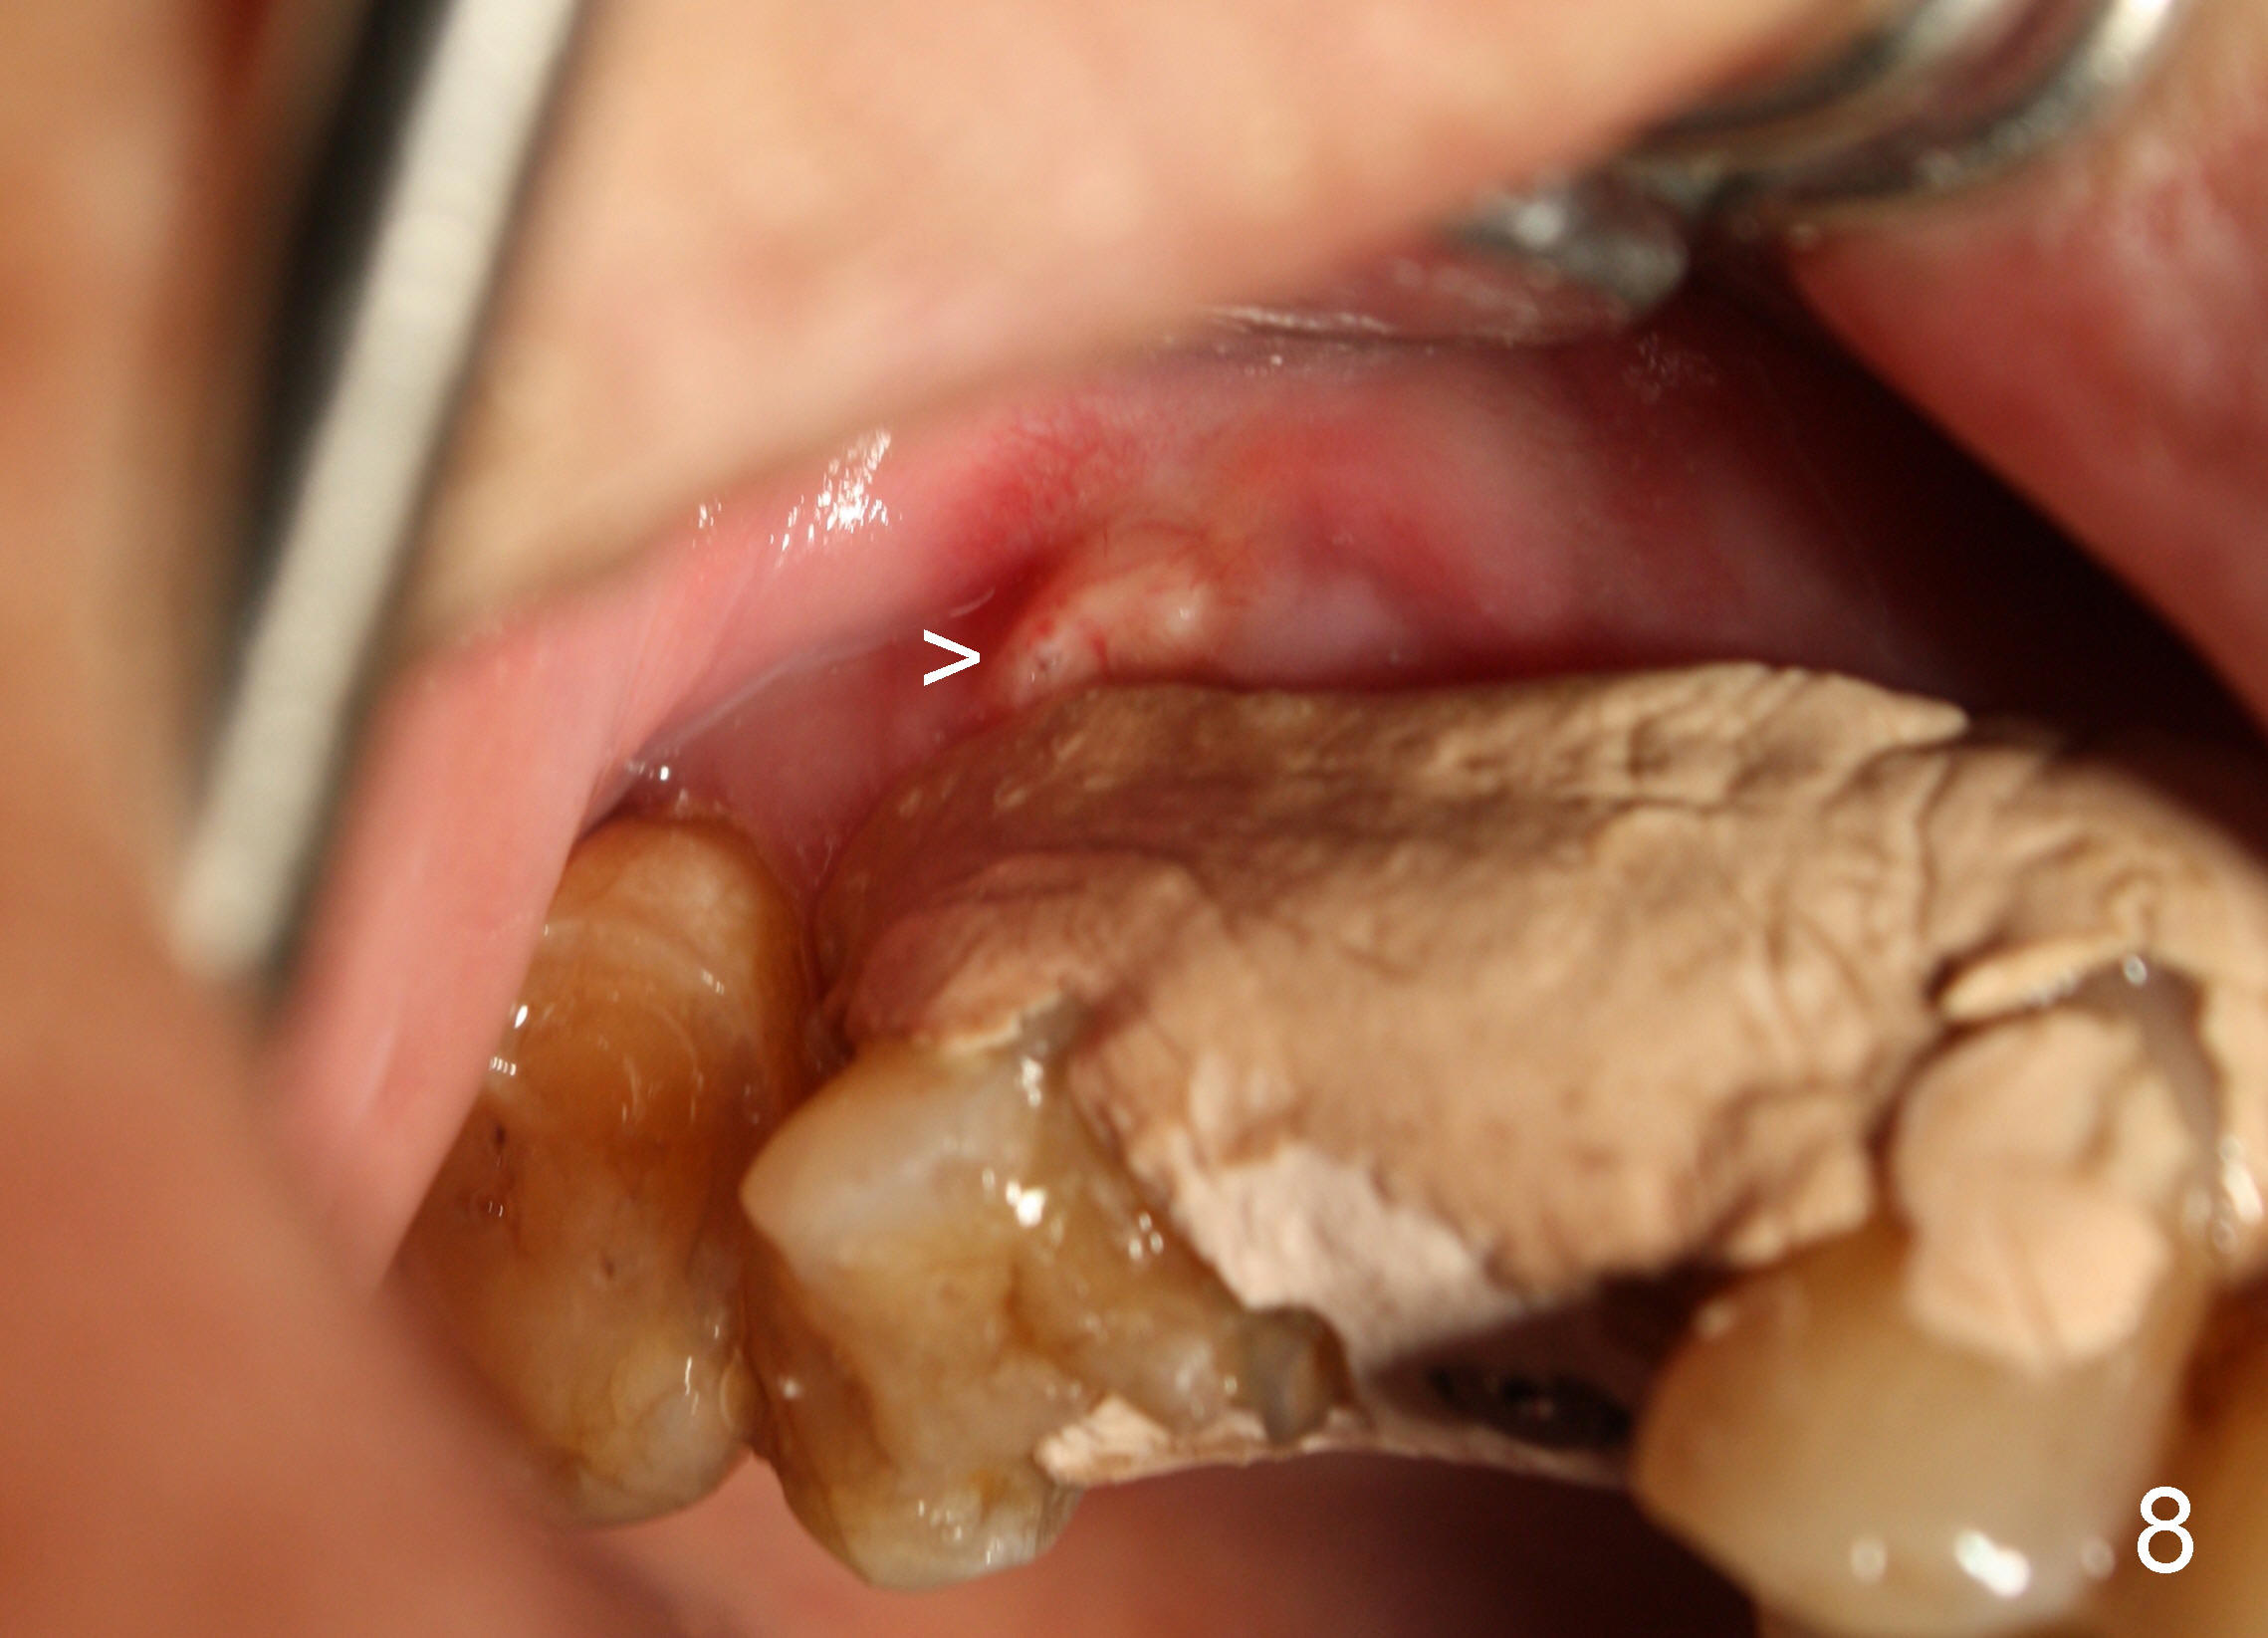

A 72-year-old man is a bruxer with #3 cusp fracture with chronic periapical radiolucency (Fig.1 *) and #4 acute crack. It appears reasonable to take care of emergency (#4 extraction and immediate implant (Fig.3-7: 4.5x20 mm, 45 Ncm)) followed by root canal therapy or extraction for #3. Eight (Fig.8) and 14 (Fig.9-11) days postop, the patient is doing fine and the wound heals normally. But he does not agree any treatment for #3, since it is asymptomatic in spite of a fistula associated with the tooth (Fig.8,9 >). Three months postop, the patient is still asymptomatic and is ready for #4 restoration since the tooth #28 cracks. Follow-up PA shows the persistent distal gap (Fig.12 >, as compared to Fig.4), accompanied with crestal bone resorption (*). Clinically the implant has mild mobility and light tenderness. The patient still refuses #3 treatment. It appears that the implant has failed to osteointegrate. In brief, do not place an immediate implant next to active infection.